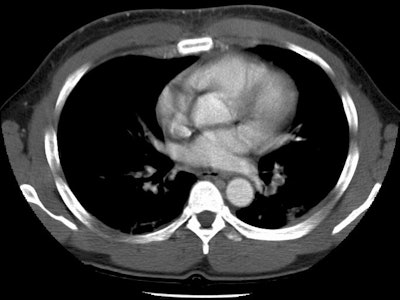

Pulmonary emboli in a lymphoma patient with SVC thrombosis

This case nicely demonstrates clot in both the superior vena cava and the left lower lobe segmental pulmonary arteries. There is also a small clot in a left upper lobe segmental vessel.